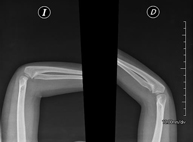

- Osteoarticular

- RX Extremidades

Técnica mediante la cual, utilizando rayos X, se obtienen imágenes del interior de las extremidades para su estudio, especialmente de los huesos. Indicaciones: traumatismo, infecciones articulares.